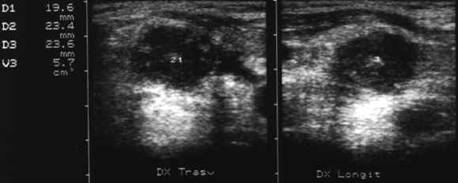

Femeie de 34 ani. Gusa nodulara in tratament supresiv cu tiroxina. Durere intensa laterocervical dreapta, cu evidentierea unei tumefactii dureroase la palpare.

Formatiunea nodulara are margini neregulate, de 22x21x23mm (5,7 cc), marcant hipoecogena, cu stratificari de ecouri spre versantul posterior. Nodulul nu era prezent in ecografia efectuata in urma cu 4 zile.

Aceeasi pacienta. Absenta vascularizatiei in interiorul nodulului, atat la doppler color cat si in powerdoppler; se evidentiaza un vas care decoleaza marginea inferioara a nodulului.